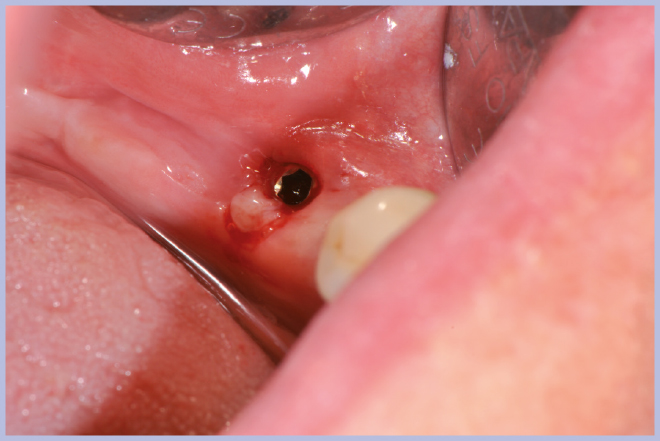

Viene quindi richiesto al tecnico di modificare in laboratorio la mascherina radiologica mediante il posizionamento delle boccole di guida adatte agli impianti da posizionare (Exacone® 6.5 e Exacone® 3,3×8) in asse con gli analoghi del modello Master 3D ed eliminando il repere radiologico standardizzato, trasformandola così nella dima chirurgica (Figg. 14, 15). Si procede quindi alla prova della mascherina sulla paziente per verificarne la stabilità e la corrispondenza esatta con il modello Master 3D (Fig. 16). La seduta chirurgica con tecnica flapless, guida chirurgica e Frese Zero1 dedicate non presenta alcuna difficoltà ; al termine dell’inserimento si posizionano sugli impianti tappi di guarigione bassi per permettere loro di guarire con tecnica sommersa (Figg. 17-27). Si effettua nella stessa seduta una CBCT che dimostra che la posizione clinica degli impianti risulta sovrapponibile a quella progettata dagli Autori (Figg. 28-30).

- Figg. 17, 18 – Passaggio dei mucotomi guidati dalla mascherina chirurgica

- Fig. 18

- Fig. 22 – Posizionamento impianto Exacone® Ø 3,3 con tappo basso